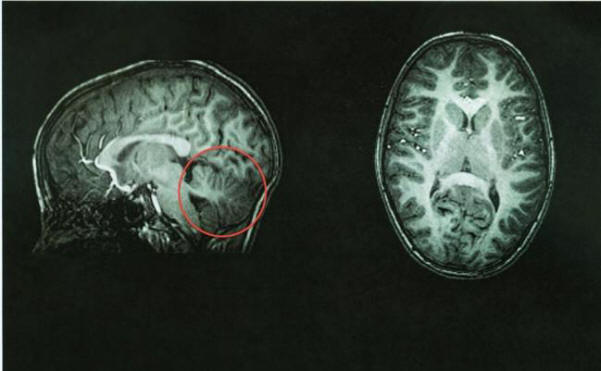

Običajna možganska tomografija, možgan v rdeči barvi

Po tomografiji so zdravniki takoj ugotovili izvor težave – njen možganov ni bil. Prostor, kjer bi moral biti prazen. Tole možgansko območje je bilo napolnjeno s cerebrospinalno tekočino, zagotavlja zaščita pred boleznijo. Vretenca ima približno 10 odstotkov skupni volumen možganov, vendar vsebuje 50 odstotkov nevronov.

Težave s cerebelarno lahko privedejo do hudih duševnih zaostalost, motnje gibanja, epilepsija ali potencialno smrtonosno kopičenje tekočine v možganih. Vendar pa na pri tej ženski je pomanjkanje možganca privedlo le do blage pomanjkljivosti gibalne in zmerne težave z govorom, kot so rahlo zdrobljene izgovorjava.

Zdravniki te učinke opisujejo kot “manj kot morda pričakujte, “in pravijo, da njen primer poudarja neverjetno plastičnost možganov.